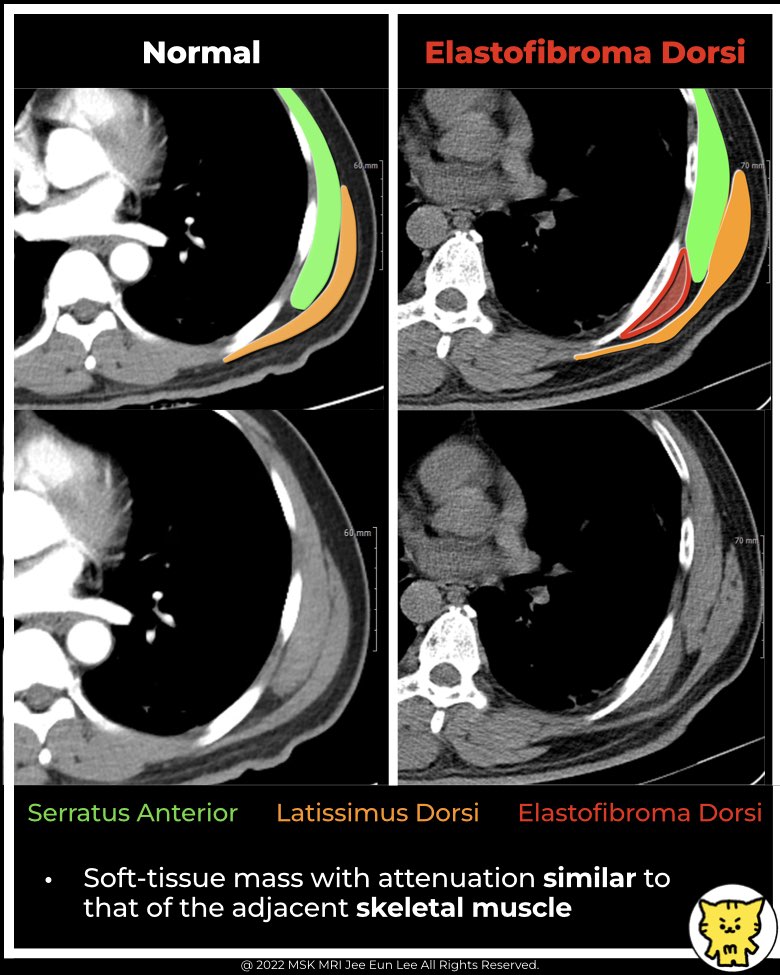

- Found deep to the serratus anterior and latissimus dorsi muscles.

✅ CT Findings

- Poorly defined soft-tissue mass.

- Attenuation similar to adjacent skeletal muscle.

- Located in the infrascapular or subscapular region.